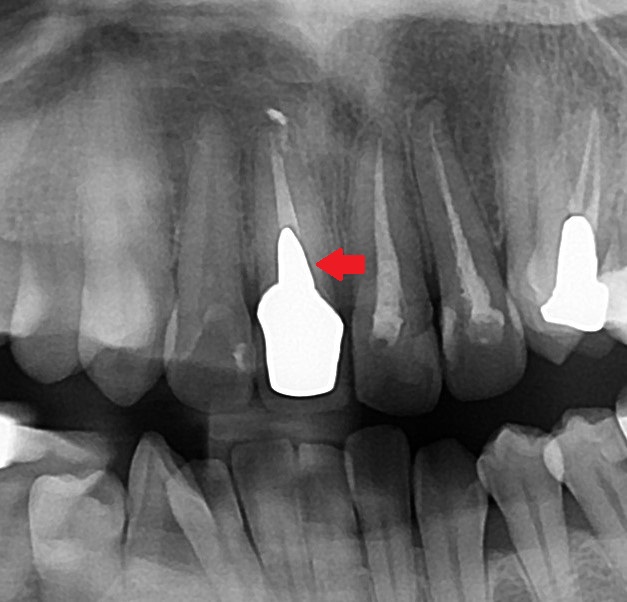

今回の患者さんもエックス線写真で確認してみると、

白く金属が写っていますが、歯の中に差し込んであるメタルコアが見られます。

メタルコアは外して、

ファイバーコアを使って土台を立て直します。